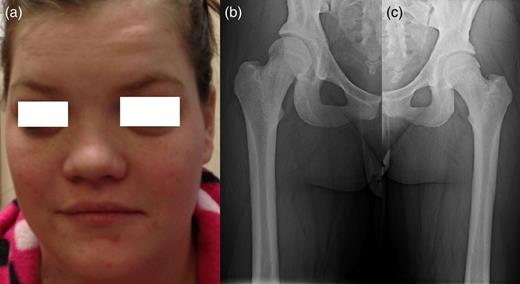

A 25-year-old female patient presented with 1-year history of occipital headache. The headache was increasing with coughing, sneezing and bending over. She had also complaints of intermittent bilateral hand numbness and bilateral feet burning. She was evaluated with magnetic resonance imaging (MRI), which showed Chiari I malformation with a 7 mm descent of cerebellar tonsils (Fig. 1 a and b). Computed tomography demonstrated diffuse calvarial thickening and loss of the medullary space (Fig. 2). Her past medical history was consistent with left eye surgery due to amblyopia when she was a child and she was blind in her left eye. Radioactive 131I treatment had been given due to the Graves’ disease and hyperthyroidism; therefore, she was hypothyroidic and was using levothyroxine daily. Her mother also was operated on because of the Chiari malformation. She had four siblings, and they did not have any pertinent medical history. Her physical examination revealed prominent occipital area and midfacial hypoplasia. Increased cortical thickness in her long bones was also demonstrated (Fig. 3 a–c). There were no abnormal findings on neurological examination except of left eye amorozis. The patient underwent surgery for decompression of posterior fossa. Large enough posterior fossa craniectomy with C1 laminectomy was performed with SSEP and MEP monitoring. Dura was opened in ‘Y’ shape, and duraplasty was performed with the pericranium. Arachnoid was kept intact. Her headaches improved significantly in postoperative period. She developed superficial wound infection, which was treated with simple washout and antibiotics.

Patients' picture showing midfacial hypoplasia on the face (a), x-ray graphy of the right femur (b) and x-ray of left femur (c) showing diffuse cortical thickening.